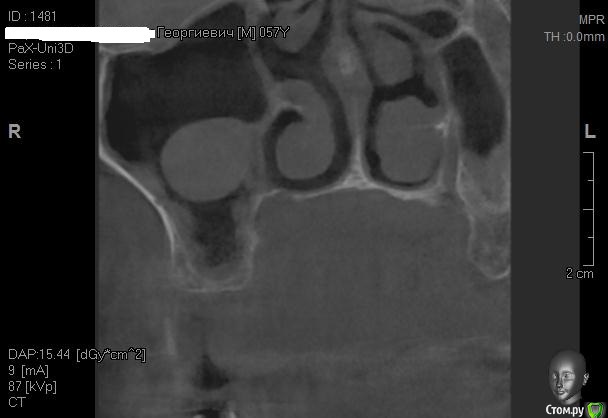

Kostoprav Опубликовано 26 апреля, 2015 Поделиться Опубликовано 26 апреля, 2015 Всем доброго времени суток коллеги!Проблема в следующем- высокая септа и мукоцеле на медиальной стенке пазухи.Мой план: сделать два окна в пазуху по обе стороны от перегородки, аккуратно попробовать отслоить слизистую и если получиться не порвать ее установить два болта не трогая кисту. В случае тотального разрыва мембраны спилить перегородку, убрать мукоцеле, зашить пазуху и повторно пойти на синуслифт через 2 месяца.Хотелось бы услышать Ваши варианты дорогие коллеги. 1 Ссылка на комментарий

Kostoprav Опубликовано 28 апреля, 2015 Автор Поделиться Опубликовано 28 апреля, 2015 (изменено) Пришлось пойти по варианту №2. слизистая пазухи в месте прикрепления к септе просто расползлась да так что в кучу не собрать. Спилил аккуратно перегородку, убрал мукоцеле (откачал с нее 2 мл. остальное убрал в месте с оболочкой зажимом), заштопал все герметично правда вот теперь думаю, правильно ли сделал что наглухо ушил, может дренаж оставить нужно было? Изменено 28 апреля, 2015 пользователем Kostoprav Ссылка на комментарий

Bier Опубликовано 28 апреля, 2015 Поделиться Опубликовано 28 апреля, 2015 все хорошо, кроме диагноза, это не мукоцелле ) Ссылка на комментарий

kriokov Опубликовано 28 апреля, 2015 Поделиться Опубликовано 28 апреля, 2015 а что? ретенционая 1 Ссылка на комментарий

Bier Опубликовано 30 апреля, 2015 Поделиться Опубликовано 30 апреля, 2015 По цитирую: "мукоцеле отличается более агрессивным ростом с разрушением костных стенок и прорастанием в окружающие ткани, часто в глазницу. Химический состав жидкости при мукоцеле, при одонтогенной кисте и при ретенционной кисте различен. Так же, как и структура кистозных стенок." Нина Каграманян "Мне часто приходится объяснять разницу между мукоцеле и ретенционной кистой, а эта разница принципиальна. Действительно, мукоцеле - это образование с агрессивным ростом, которое деформирует стенки пазух либо разрушает, прорастая в соседние анатомические области. Наиболее частая локализация - лобная пазуха. Основная причина формирования мукоцеле - блок соустья пазухи + операция в синоназальной области в анамнезе. Основное лечение мукоцеле - хирургическая марсупиализация."Ксения Клименко "Это проблема перевода. В англоязычных источниках ретенционные кисты часто называют mucocele, а по-русски это совершенно разные вещи." Игорь Горбоносов "Игорь, на самом деле путаница и среди зарубежных авторов встречается. Есть понятие mucocele, а есть mucous retention pseudocyst." Ксения Клименко 7 Ссылка на комментарий